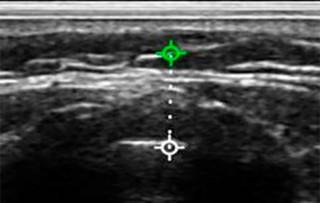

Para la correcta medición de la grasa pretraqueal: se colocó al paciente en estado consciente en posición supina con cabeza en hiperextensión (posición de olfateo), con el objetivo de exponer el cuello para su medición. Se utilizó el ultrasonido de la marca Sonowireless Plus I adaptado a un transductor lineal con frecuencias de 7.5 y 10 MHz. El ultrasonido se conectó de forma inalámbrica a un teléfono celular personal para visualizar imagen y tomar medidas con herramienta de regla incluida en la aplicación «WirelessKUS» (Figuras 1 y 2). El transductor se colocó entre la piel y membrana cricotiroidea. Para visualizar la grasa pretraqueal del paciente se evaluó la distancia comprendida entre la piel y el anillo traqueal.

Figura 1: Toma de medida de grasa pretraqueal con ultrasonido convencional a paciente en consulta preanestésica.